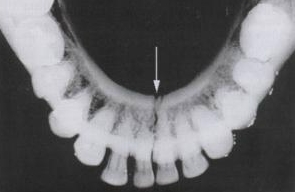

Standard Mandibular Series: Occlusal View

• Special Dental Film

• Symphysis

• Alveolar Processes